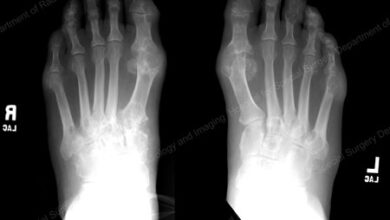

ĐIỀU TRỊ GÚT TRÊN BỆNH NHÂN TĂNG HUYẾT ÁP Ở TUYẾN CƠ SỞ

Ths.Bs Phạm Thị Thuyên Giới thiệu và dịch tễ học Gút hiện hành trong dân số từ <1 đến 4%.…